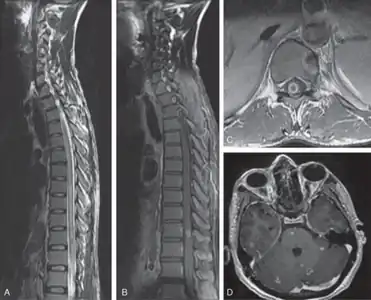

Myeloradiculopathy in tuberculous meningitis[16]-a) Long segment myelitis b,c) intramedullary tuberculoma at D10 level d)multiple tuberculoma involving cerebrum, cerebellum, and brainstem